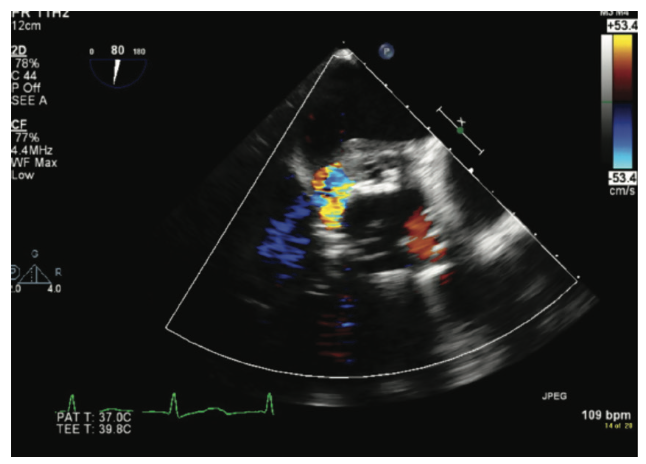

A large vegetation extended from the aortic root into the left atrium with associated moderate to severe MR.